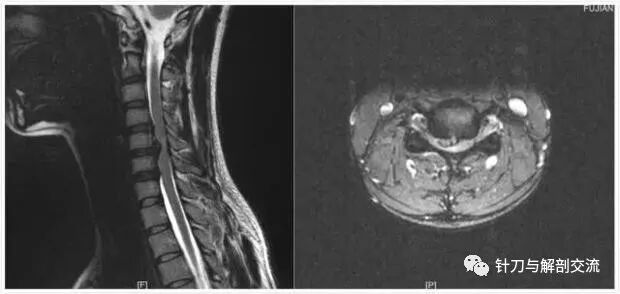

颈椎磁共振表现为:颈椎间盘突出,脊髓受压。

辅助检查:颈椎正侧位片:生理曲度变直,颈部脊柱向左侧弯,寰枕间隙变窄、C3/4钩椎关节变尖。颈椎磁共振:C5/6椎间盘轻度突出。